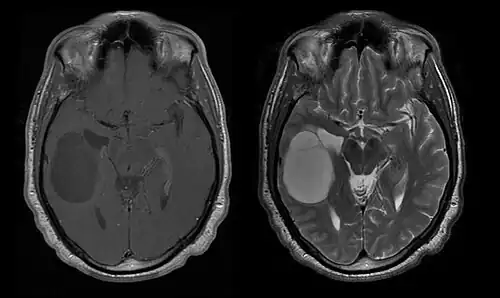

A tomografia computadorizada (TC) e a ressonância magnética (RM) podem detectar efetivamente uma neoplasia no cérebro. A RM é mais sensível que a TC para identificar lesões, mas contraindicações para pacientes com marcapasso cardíaco, próteses incompatíveis, clipes metálicos e outros. A TC continua sendo o método de escolha para detectar calcificações dentro de lesões ou erosões ósseas da calota craniana ou da base. A utilização de agentes de contraste, que são iodados no caso da TC e paramagnéticos ( gadolínio ) no caso da RM, permite a aquisição de informações sobre a vascularização e integridade da barreira hematoencefálica, uma melhor definição do tumor tumoral comparado ao edema circundante e à geração de hipóteses sobre o grau de malignidade . O exame radiológico também permite avaliar os efeitos mecânicos e consequentes alterações nas estruturas cerebrais decorrentes do tumor, como hidrocefalia e hérnias, cujos efeitos podem ser fatais. Finalmente, na preparação para a cirurgia, esse diagnóstico pode ser usado para determinar a localização da lesão ou a infiltração do tumor em áreas vitais do cérebro. Para isso, a RM é mais eficiente que a TC, pois pode fornecer imagens tridimensionais.

As ferramentas de diagnóstico por imagem radiológica destacam a mudança no tecido neoplásico em comparação com o parênquima cerebral normal (através de alterações na densidade do tecido fotografado eletronicamente na TC e na intensidade do sinal na RM). Como a maioria dos tecidos patológicos, os tumores também são reconhecidos por um acúmulo aumentado de água intracelular. Na tomografia computadorizada aparecem hipodensa, ou seja, de menor densidade que o parênquima cerebral, na tomografia de ressonância magnética nuclear com relaxamento spin-lattice T 1 hipointenso e em relaxamento spin-spin T 2 bem como a ponderação de prótons (PD) hiperintensa.

A tomografia computadorizada do cérebro normalmente mostra uma massa de tecido que pode ser realçada por qualquer contraste. Na TC, os gliomas de baixo grau geralmente parecem isodensos ao parênquima normal e, portanto, podem não apresentar realce pelo contraste. Da mesma forma, lesões na fossa posterior do crânio são difíceis de identificar na TC. Consequentemente, os resultados dessa tomografia isoladamente nem sempre são suficientes para fins diagnósticos. Em casos duvidosos, o uso da ressonância magnética mais sensível é essencial.

Na ressonância magnética, um tumor intracraniano aparece como uma lesão maciça que pode se tornar mais luminescente após o uso do agente de contraste. No entanto, há sempre uma anomalia de sinal na ressonância magnética, que indica a presença de neoplasia ou edema vasogênico. Normalmente, o aumento da luminescência (realce pelo contraste) é indicativo de um tumor de grau mais alto de malignidade. Um anel contrastante é característico do glioblastoma, com a porção luminescente correspondendo à parte vital do tumor maligno e a área mais escura-hipointense à necrose tecidual.

Linfomas primários do SNC

O linfoma primário do sistema nervoso central é responsável por cerca de 2 por cento para 3 por cento de todos os tumores cerebrais em pacientes com um sistema imunológico normal. Ocorrem mais frequentemente em homens com mais de 55 anos até 60 anos acima. Quase metade de todos os linfomas ocorrem em pacientes com mais de 60 anos e cerca de um quarto em pacientes com mais de 70 anos. anos acima. A incidência parece aumentar com a idade, mas a razão ainda não é clara. Pacientes com sistema imunológico enfraquecido correm maior risco de desenvolver linfoma do SNC, portanto, aqueles que tiveram um transplante de órgão têm uma imunodeficiência congênita ou doença autoimune ou estão infectados com o vírus da imunodeficiência humana. Os linfomas cerebrais associados ao HIV estão associados ao vírus Epstein-Barr, particularmente em pacientes com contagens de linfócitos CD4 abaixo de 500 células por milímetros cúbicos no sangue. A maioria dos linfomas do SNC são linfomas difusos de grandes células B.

Os pacientes sofrem de uma variedade de sintomas característicos de uma lesão maciça focal ou multifocal. A RM geralmente mostra tumores com realce homogêneo de contraste dentro da substância branca periventricular profunda. Multifocalidade e realce não homogêneo são típicos para pacientes com sistema imunológico enfraquecido. A análise do linfoma do SNC é extremamente importante no diagnóstico diferencial das neoplasias cerebrais. Ressalta-se que a administração de corticosteróides pode levar ao desaparecimento completo do realce, dificultando o diagnóstico das lesões. Consequentemente, se o linfoma do SNC for considerado no diagnóstico diferencial, os corticosteróides devem ser evitados, a menos que o efeito de massa cause um problema sério e imediato no paciente.